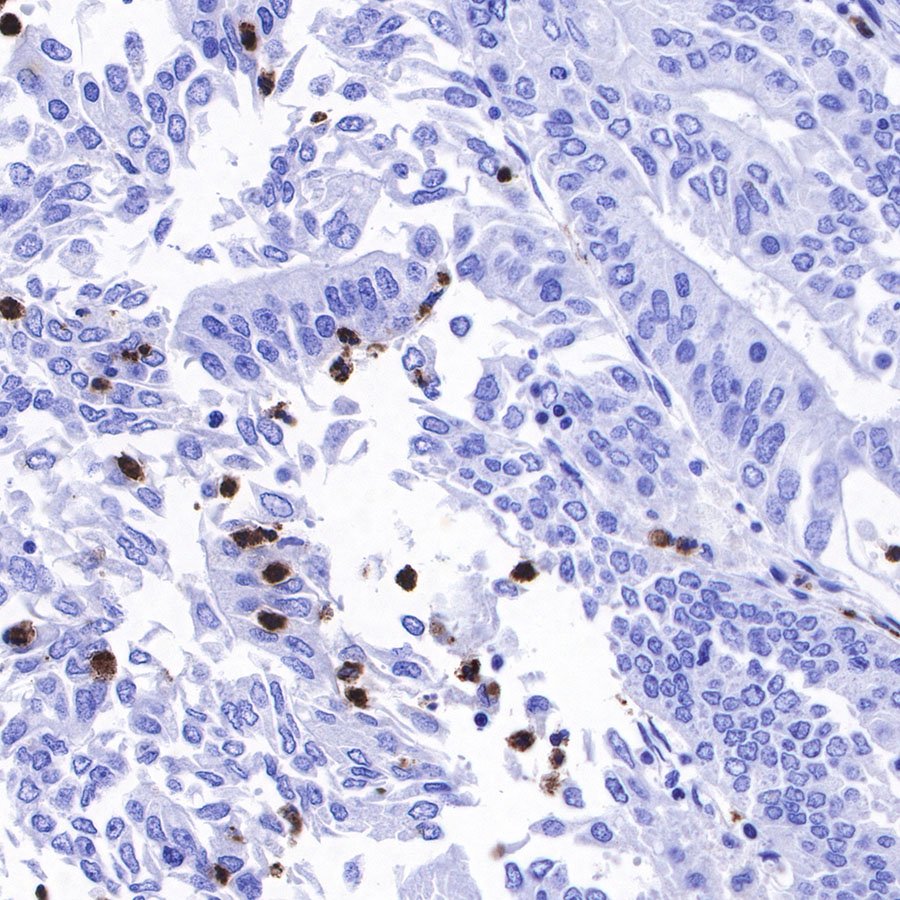

Immunohistochemistry

IHC shows positive staining in paraffin-embedded human colon cancer. Anti-Lysozyme antibody was used at 1/100 dilution, followed by a HRP Polymer for Mouse & Rabbit IgG (ready to use). Counterstained with hematoxylin. Heat mediated antigen retrieval with Tris/EDTA buffer pH9.0 was performed before commencing with IHC staining protocol.